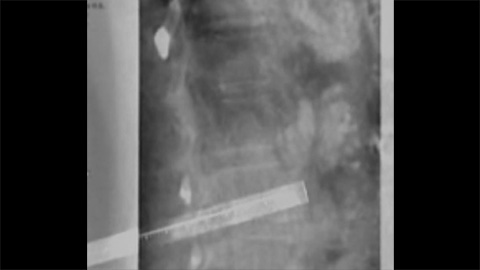

Clarity IQ produces finely tuned high-definition fluoroscopic images with superb detail to assist with needle progression to target [6].

XperGuide provides highly accurate live image guidance of each needle to a targeted position by overlaying pre-planned trajectories with fluoroscopic imaging [10].